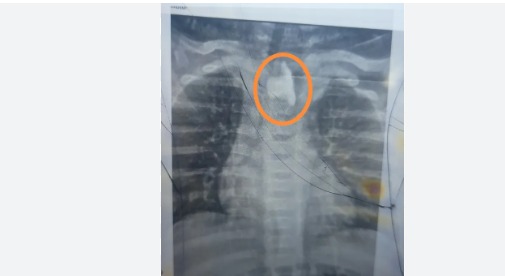

وكان الطفل دخل قسم الأطفال وهو يعاني من التهاب حاد بالشُعب الهوائية وصعوبة في التنفس، وبعد عدم استجابته للعلاج المنزلي، تم حجزه بالمستشفى وخلال الفحوصات، تم طلب أشعة عادية على الصدر، والتي كشفت عن وجود جسم غريب في الجزء العلوي من المريء، تسبب في انسداد مجرى الطعام.

وعلى الفور، جرى تجهيز الطفل طبيًا، وخضع لمنظار معدة عاجل، أسفر عن استخراج “زلطة” كانت مستقرة بالمريء منذ فترة، ومتغلغلة في الأغشية، دون علم أسرته.